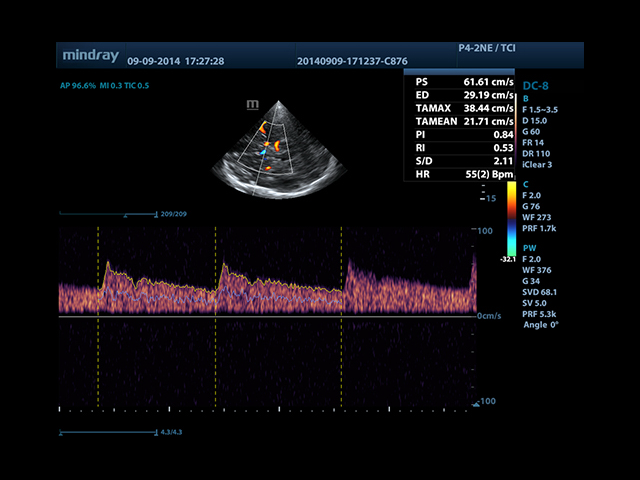

Mindray DC-8 Exp оснащен новым поколением датчиков с увеличенным количеством элементов и инновационной технологией "3T". Это позволяет достичь высокой детализации и качества изображения. Благодаря новейшей технологии iFlow, можно визуализировать даже самые мелкие сосуды и кровеносные пути.

Сверхширокополосная нелинейная обработка изображений снижает визуальные шумы на 30% по сравнению с другими системами. Технология iClear позволяет устранить зернистость изображения, а iBeam (технология пространственного компаундинга) обеспечивает высокое качество сканирования органов и тканей под различными углами.

• Smart Doppler - автоматическая подстройка расположения рамки цветового доплера и контрольного объема импульсно-волнового доплера нажатием кнопки.